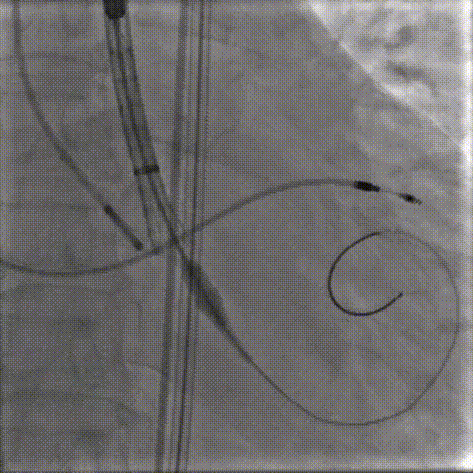

6.稳定脱钩

11.gif

7.22mm球囊后扩

12.gif

7.最终造影,形态位置(0位)良好,无瓣周漏

13.gif

术后超声探查:人工瓣膜位置正常、功能良好,主动脉口 Vmax: 102cm/s,PGmax:4mmHg,PGmean :2mmHg;VTI 估测瓣口面积达 1.7cm²,EF:33%,患者心功能得到实质性提升,生命体征平稳,手术取得圆满成功。